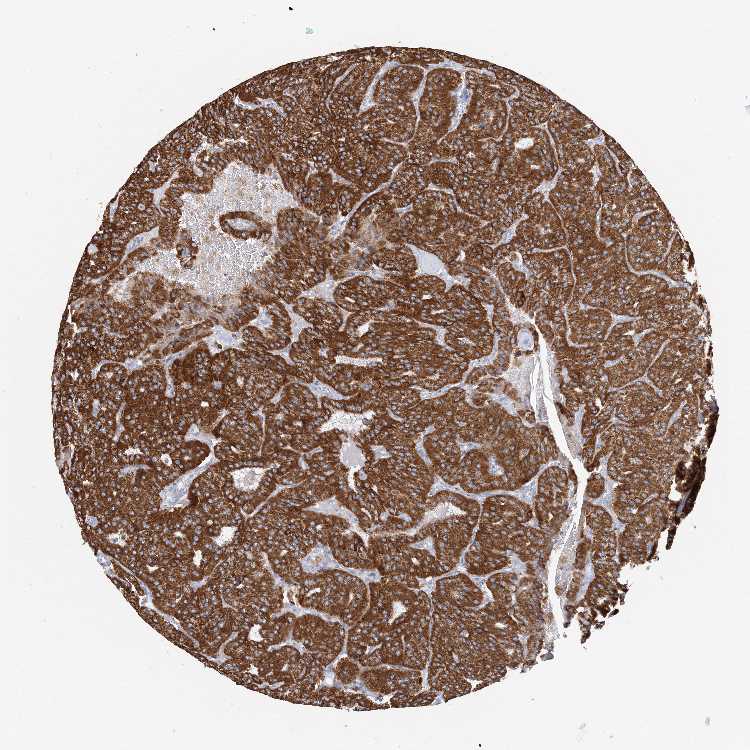

PARATHYROID GLAND - Antibody stainingi

Antibody staining in the annotated cell types in the current human tissue is reported as not detected, low, medium, or high, based on conventional immunohistochemistry profiling in selected tissues. This score is based on the combination of the staining intensity and fraction of stained cells.

Each image is clickable and will lead to virtual microscopy that enables deeper exploration of all samples and also displays staining intensity scores, fraction scores and subcellular localization as well as patient and tissue information for each sample.

Antibody HPA030947

Glandular cells High